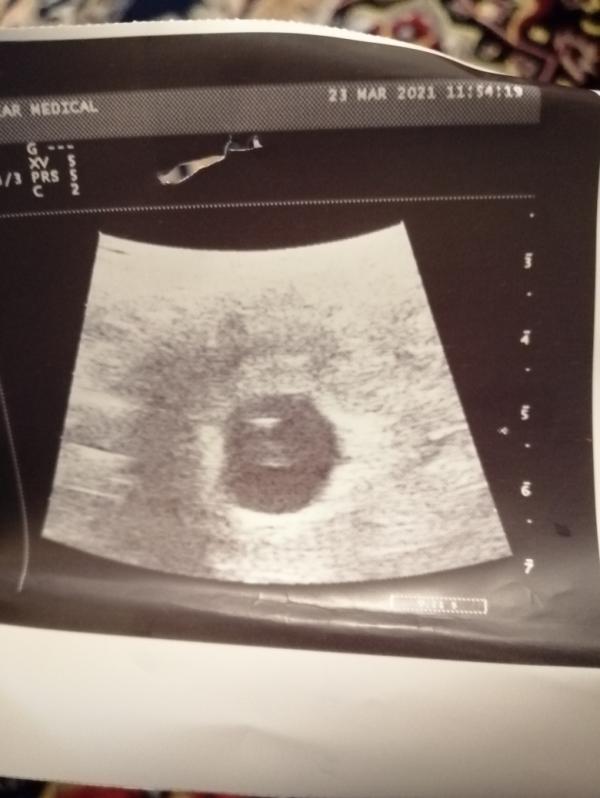

Девочки, всем привет покажите мне свои узи фото, хочу посмотреть нормальна ли у меня после вчерашнего немного переживаю 4 5 недель

Фото это не главное , важно что узист в заключении написал

Действительно что вы хотите понять по снимку УЗИ))) у вас есть сб значит плод живой,просто подождите . 5 Нед это очень мало,сб разгонится) сходите через 2 Нед на контрольное узи

@aika890 у вас очень маленький срок, я и не увидела сердцебиение и эмбриона не было. На сроке 6-7 недель уже лучше